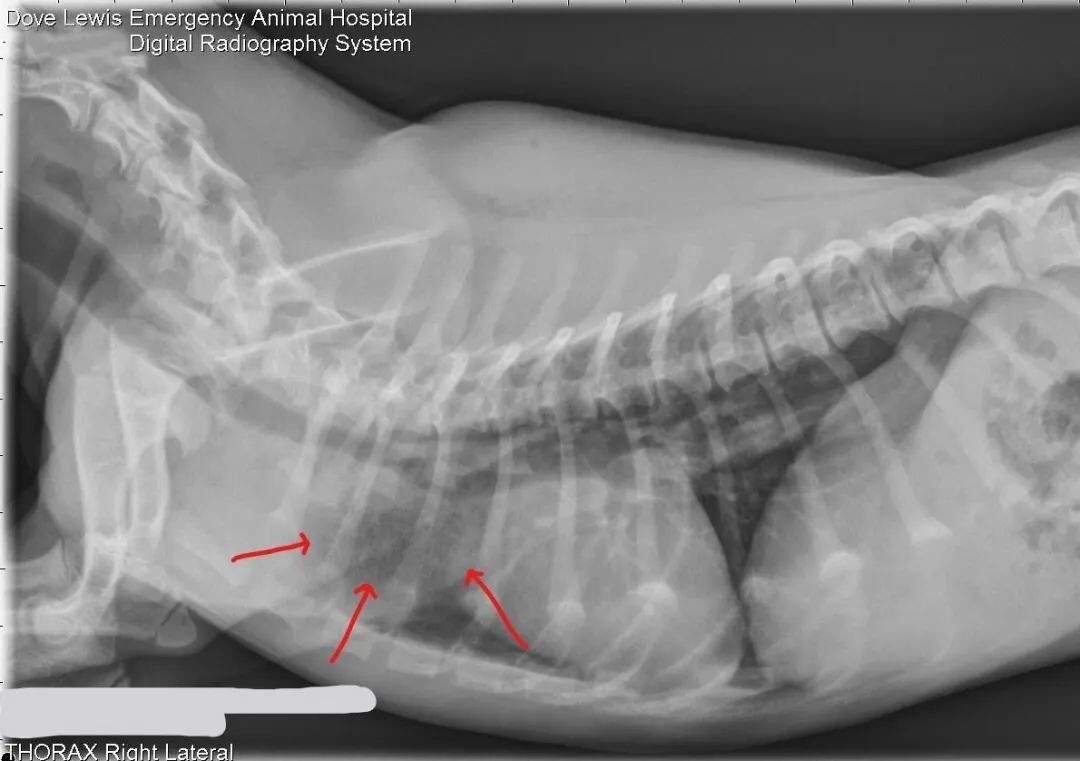

一只四个月大的雌性腊肠犬因呕吐而转诊到本文作者医院。患犬在一个月多次呕吐和腹泻,初诊兽医在做了三次检查。在腹部 X 光片和粪便检查的结果均为正常,兽医使用药物治疗。但患犬仍在进食不久后就继续呕吐,因此本病例转诊到作者医院。体检和血液学检查均正常。由于考虑患犬是返流而不是呕吐,所以安排腹部超声检查以及胸部 X 线检查。胸部 X 光片显示心影轮廓的颅侧可观察到食管有中度的局灶性扩张(图 1)。这个影像学发现的主要鉴别诊断方向是血管环畸形或食管异物。

图 1